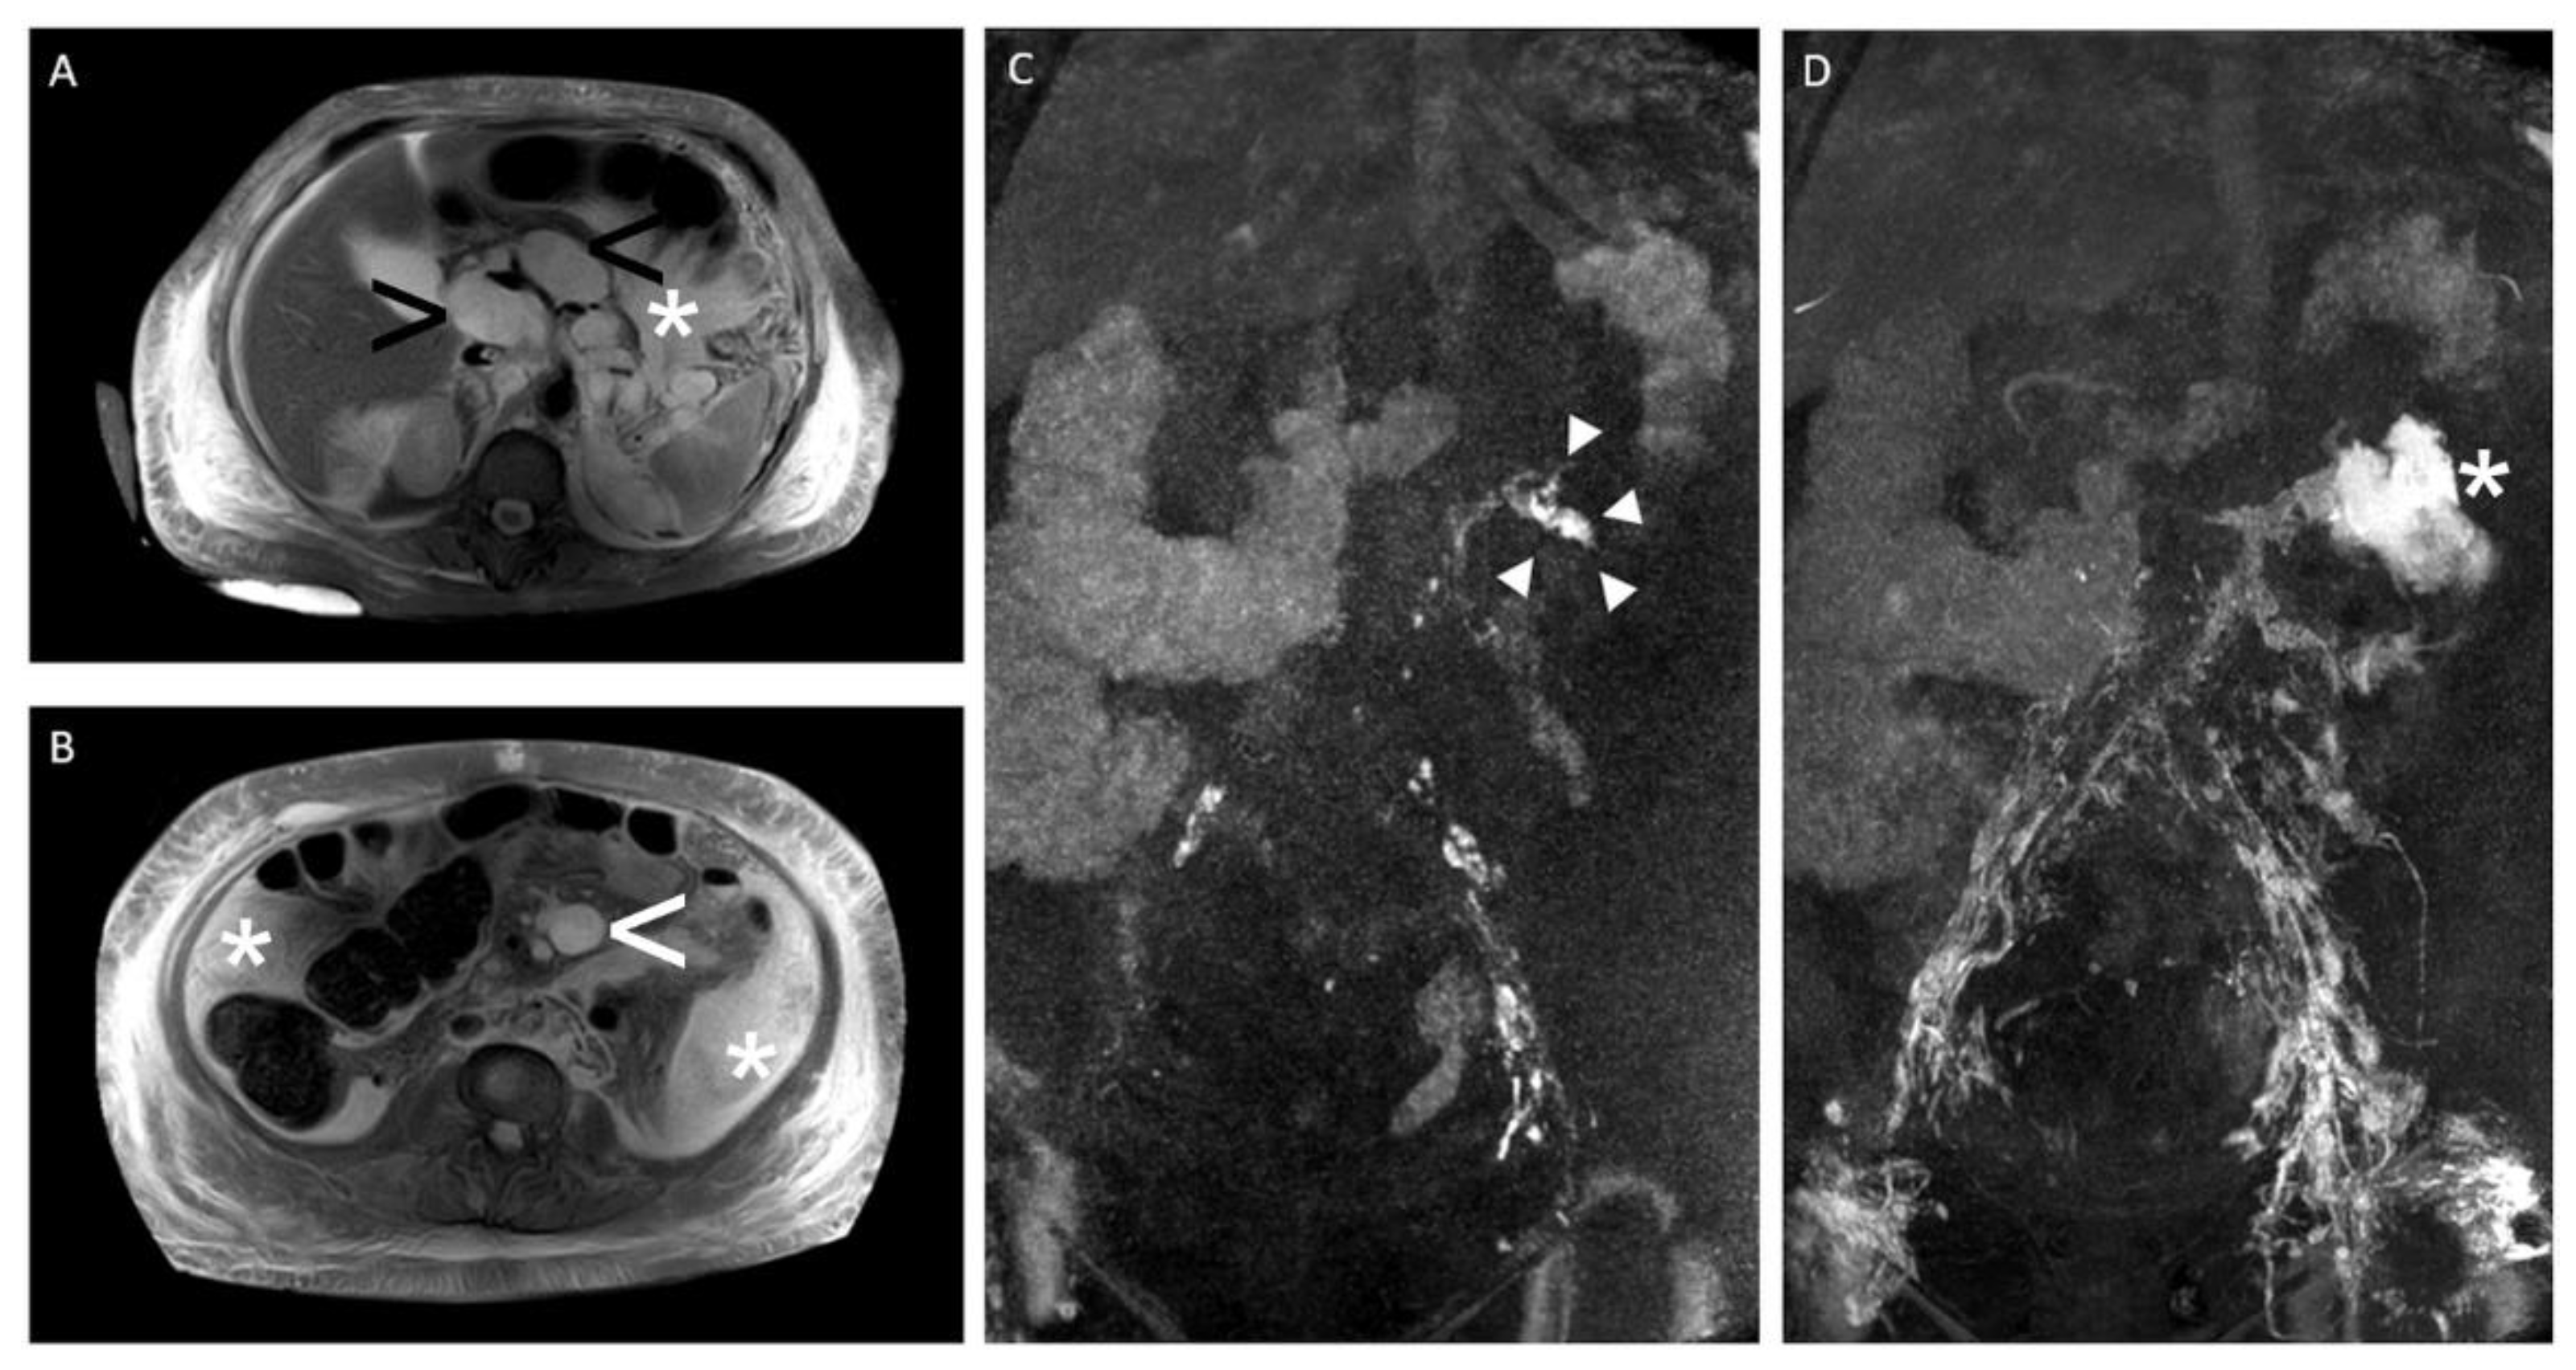

Figure 7.

“Intranodal MR lymphangiography“—A 59-year-old woman with massive refractory chylaskos (>5000 mL per day) after retroperitoneal lymphadenectomy. Note: (A,B) T2-weighted, fluid-sensitive MRI (axial plane) showing ascites (white arrowhead), massive subcutaneous lymphedema (white asterisk), and multiple cystic/necrotic retroperitoneal and mesenteric lymph node metastases (black arrowhead); (C,D) dynamic contrast material (gadolinium)-enhanced “intranodal MR lymphangiography” (coronal maximum-intensity projection) showing the fistula point with pathologic contrast material extravasation from retroperitoneal lymph ducts on the left during contrast material’s injection (white arrowhead) (C) and massive contrast material extravasation into the ascites after contrast material’s injection (white asterisk) (D).